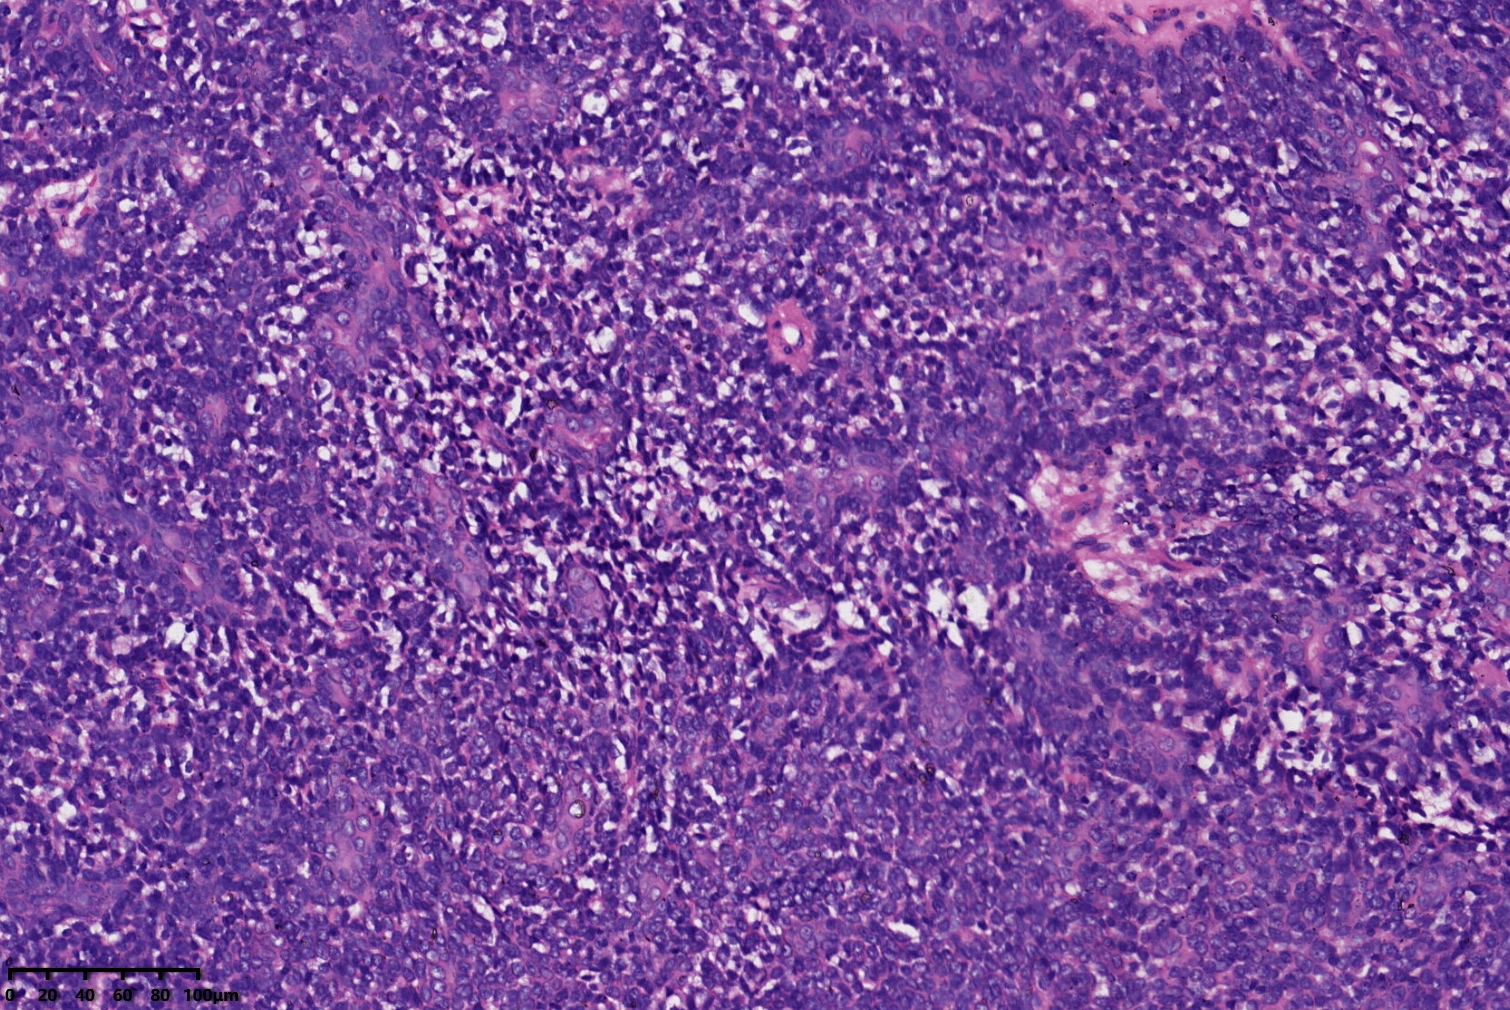

汗腺腺瘤?

背部包块

同意,有的区域像透明细胞汗腺瘤

小汗腺螺旋腺瘤